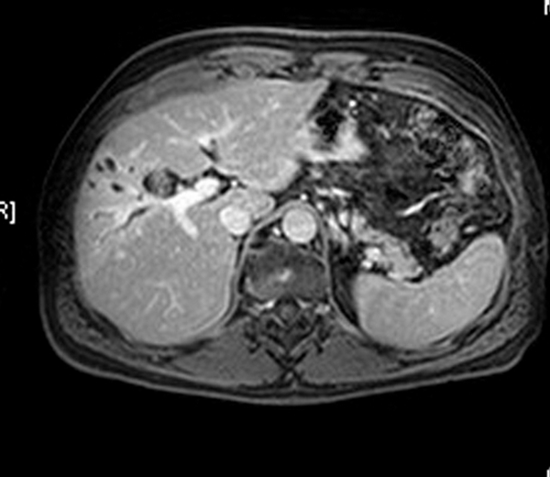

بررسی حساسیت ، اختصاصیت و دقت تشخیصی بافت سنجی کبد در ام آر آی با نرم افزار TextRAD جهت افتراق آدنوم هپاتوسلولار از هایپرپلازی ندولار کانونی کد خبر : 293323 کپی کلمات کلیدی _بافت_سنجی_کبدآدنوم_هپاتوسلولارهایپرپلازی_ندولار